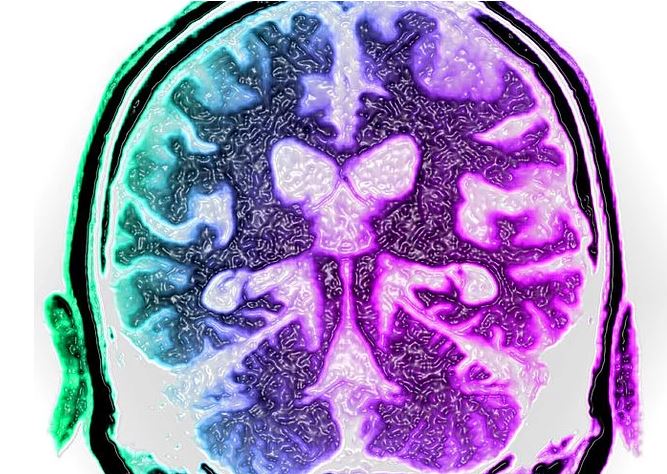

Erken dönem alzheimer hastaları arasında yapılan çalışmada alzheimer olanların beyinlerinde olmayanlara oranla çok daha yüksek miktarda herpes virüsüne rastladı.

Aslında bu çalışma başta genetik inceleme üzerine kurulmuştu. alzheimer olanların beyin hücrelerindeki genlerin sıra dışı olanlarını bulmaya çalışırken sürpriz bir şekilde uçuk virüsüyle karşılaştılar.

Çalışma alzheimer belirtisi gösteren 622 ve bu belirtileri taşımayan 322 kişiyle yapıldı.

Alzheimer belirtilerine sahip olanların daha fazla herpes ilişkisinin olması ya bu virüs hastalığa yol açıyor, ya da beyin uçukla savaşmak için alzhemier belirtileri başlatıyor olarak yorumlandı.